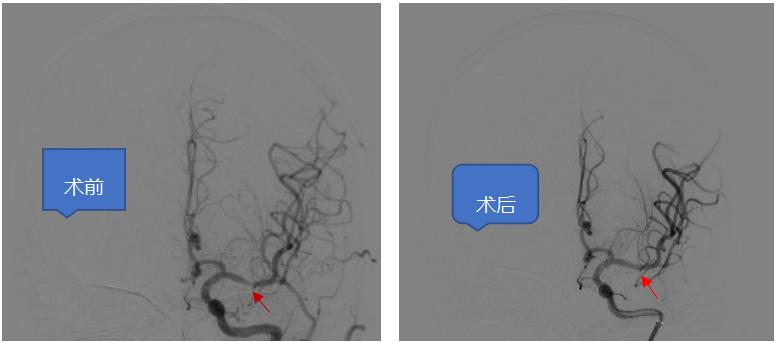

术前检查完成后,神经外科介入团队于6月14日在局麻下给患者行全脑血管造影检查提示“颅内多发动脉粥样硬化伴狭窄,左侧大脑中动脉M1段重度狭窄”。左侧大脑中动脉仅余一线,狭窄率接近99%。考虑患者反复出现脑梗死与左侧大脑中动脉狭窄有关。且其它血管对左侧大脑中动脉供血区域基本无代偿,一旦发生大脑中动脉闭塞将发生严重后果,有明确的手术指征。与患者及家属沟通病情后决定行颅内动脉狭窄血管内介入治疗。后改为气管插管全身麻醉,术中严格控制血压。因患者血管迂曲,神经外科介入团队使用多种技术手段最终成功到达狭窄部位。行左侧大脑中动脉狭窄球囊成形术后,观察30分钟后仍有残余狭窄,给于置入颅内动脉支架一枚。复查血管造影提示狭窄血管完美修复。

术前造影提示左侧大脑中动脉重度狭窄,术后血管完美修复